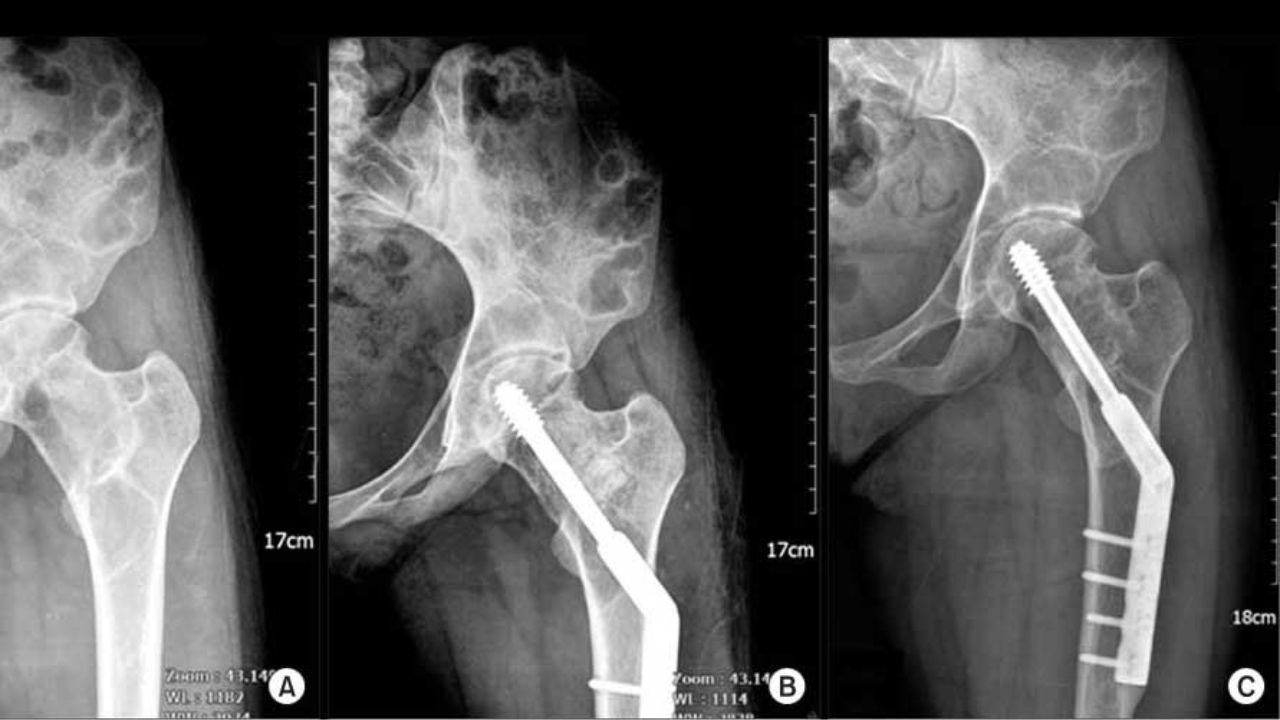

عمل جراحی

اگر بافت فیبری استخوان باعث ایجاد عوارض شده باشد یا به درمانهای دیگر پاسخ ندهد، ممکن است نیاز به جراحی باشد. جراح برای برداشتن استخوان آسیبدیده و پیوند استخوان اقدام میکند.

همچنین در صورت شکستگی استخوانها نیز گاهی لازم است عمل جراحی انجام شود.